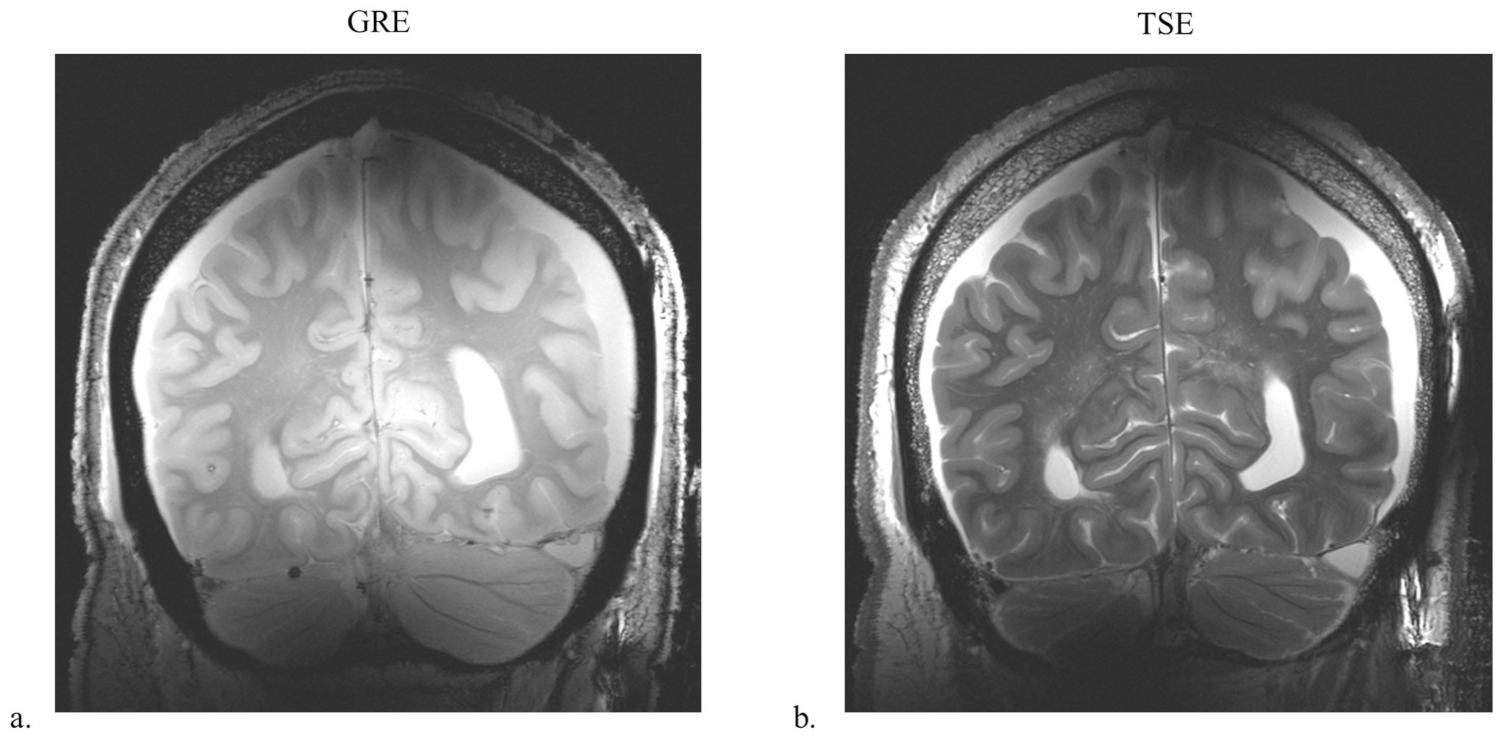

3.3. Comparison of the Dipole, Monopole, and Sleeve Antenna Arrays with Human Model and Human Cadaver Images with the Sleeve Antenna Array